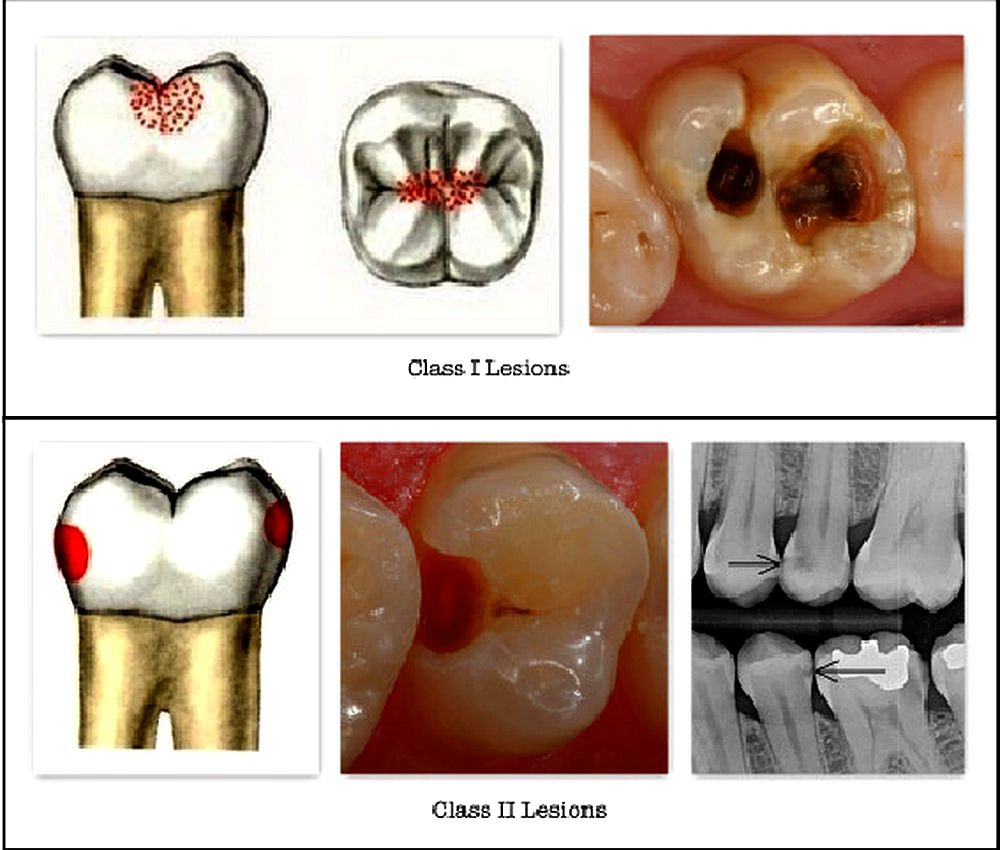

DENTAL CARIES : Radiographic Interpretation Of Dental Caries

caries dental radiographic classification disease interpretation teeth

12: Diagnosis And Management Of Dental Caries | Pocket Dentistry

caries dental dentistry clinical diagnosis icdas management pediatric surfaces tooth lesion smooth teeth occlusal enamel criteria grading pit severity fissure